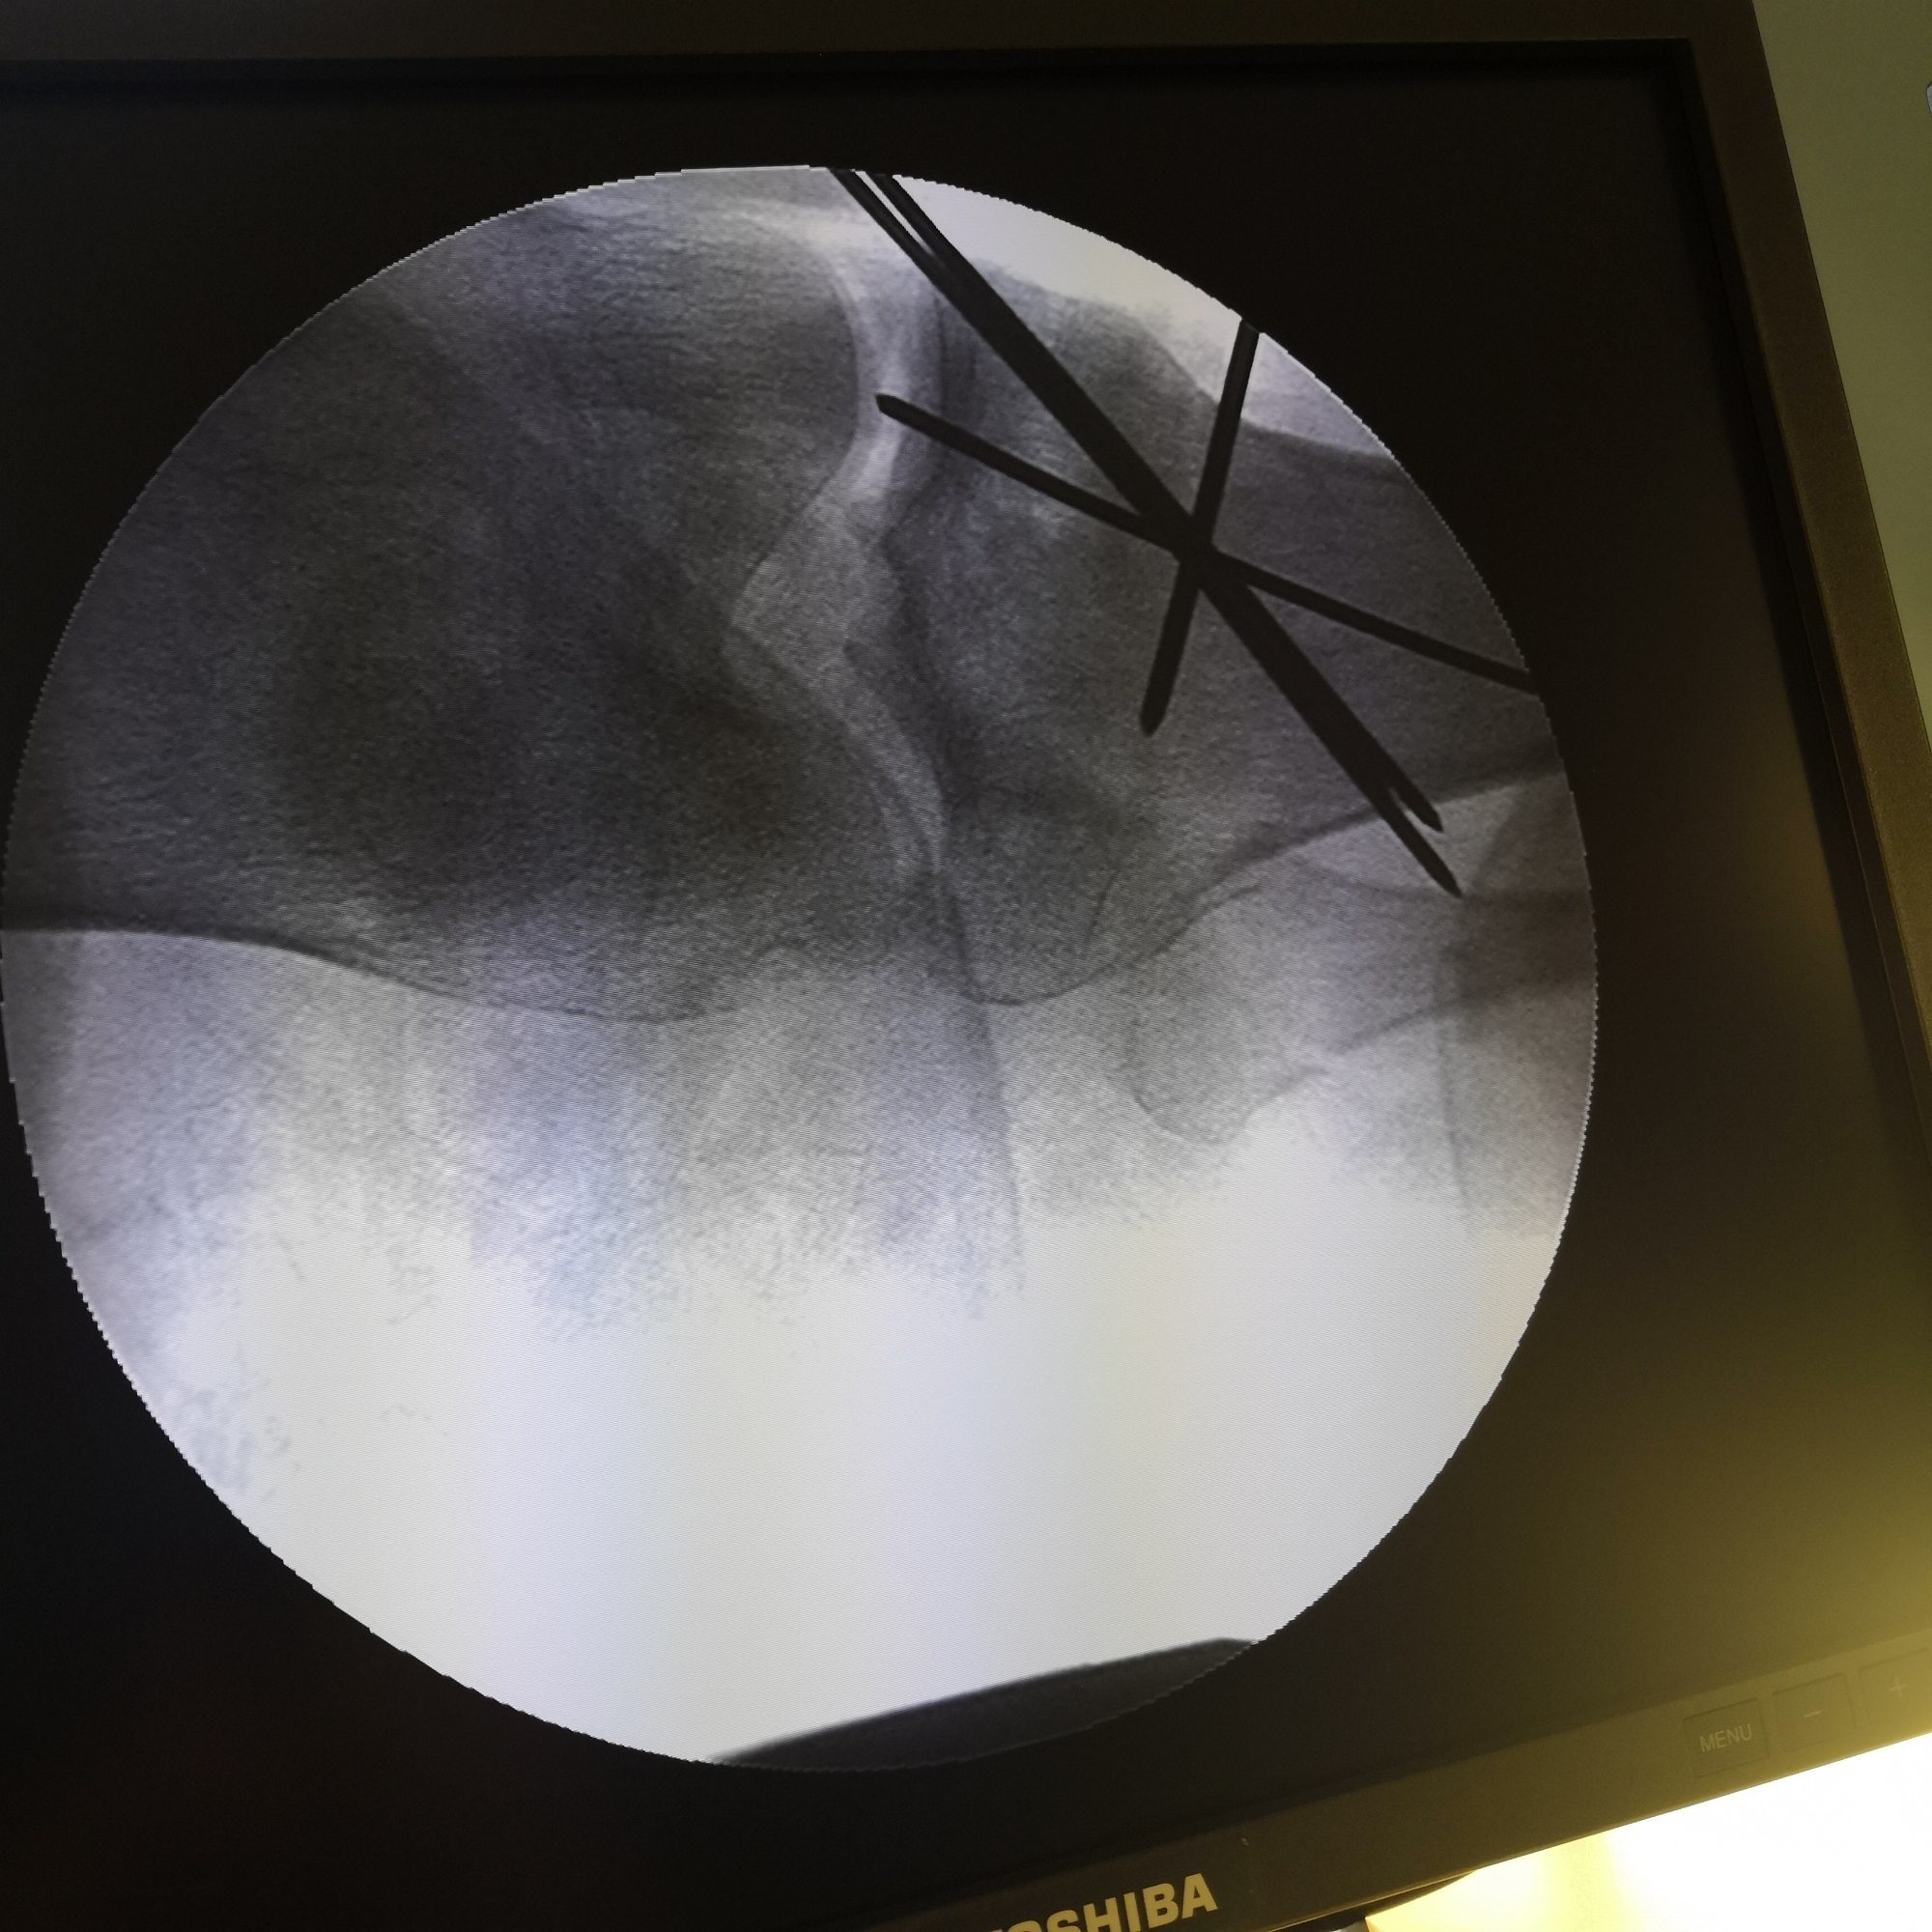

麻醉下行下肢牵引,同时对分离的胫骨平台进行手法复位。维持位置透视判断复位情况,及进一步调整牵引。

牵引复位前X光片